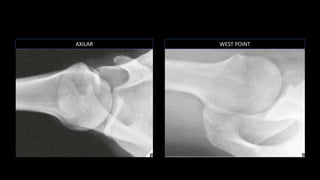

O documento aborda lesões no ombro, dividindo-as por faixas etárias: fraturas de clavícula em crianças, luxações em adultos e fraturas do úmero proximal em idosos. Descreve também técnicas de avaliação radiográfica e suas variações, incluindo incidências específicas para diagnóstico. Além disso, são mencionados métodos de imagem alternativos para a avaliação de partes moles e condições articulares.